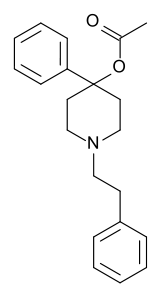

4-Phenylpiperidines

Others

Structures

| Other phenylpiperidines | |||

|---|---|---|---|

Alvimopan Alvimopan |

Loperamide Loperamide |

LS-115509 LS-115509 |

Picenadol Picenadol |